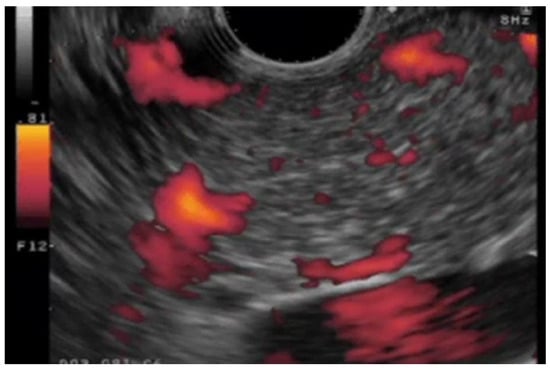

(C)

DFI-EUS (32/33 cases, 97%) is significantly superior to e-FLOW EUS (24/33 cases, 73%) for differential diagnosis between mural nodules and mucous clots in IPMN and between solid gallbladder lesions and gallbladder sludge (Figure 7) [44]. Although no clear conclusion can be drawn due to including gallbladder disease in this study, DFI-EUS is expected to be a useful tool for differential diagnosis between mural nodules and mucous clots in IPMN and will likely replace CH-EUS in the future.

Figure 7. The sensitivity of vascularity for detecting a mural nodule in IPMN using each modality. (a) e-Flow EUS: No vessels are detected in the mural nodule. (b) DFI-EUS: Detected a vessel in the mural nodule. (c) CH-EUS: Detected a mural nodule with vascularity.